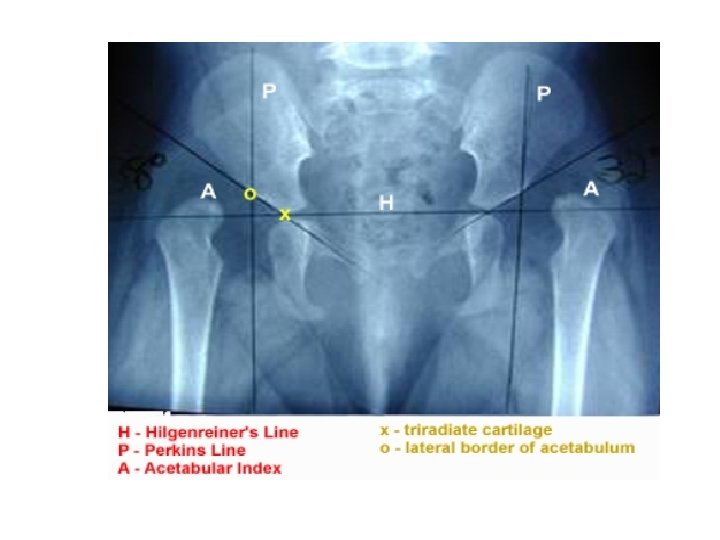

Developmental Dysplasia Of The Hip DDH Definition Dysplasia

Developmental Dysplasia Of The Hip DDH Definition Dysplasia

Developmental Dysplasia Of The Hip DDH Definition Dysplasia

Developmental Dysplasia Of The Hip DDH Definition Dysplasia

Developmental Dysplasia Of The Hip DDH Definition Dysplasia

Developmental Dysplasia Of The Hip DDH Definition Dysplasia

Developmental Dysplasia Of The Hip DDH Definition Dysplasia

Developmental Dysplasia Of The Hip DDH Definition Dysplasia